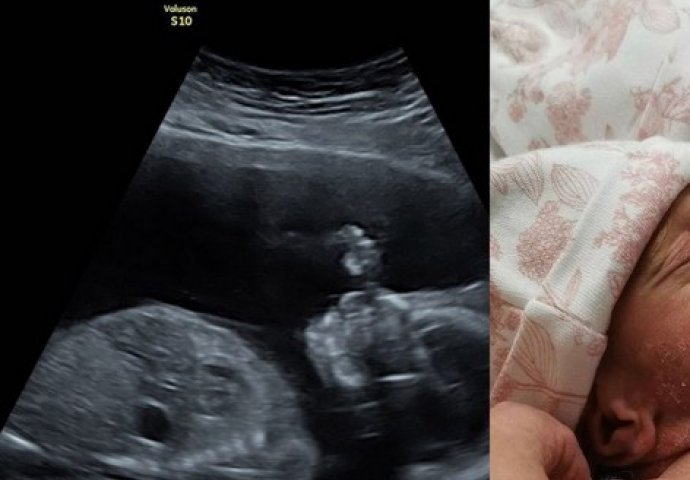

Arija i Skajlar Morgan Troden su na svijet došle carskim rezom, potpuno zagrljene. Fotografiju je napravila zapanjena babica, koja je prokomentarisala da su i ona i ljekar ostali bez teksta kada su ih vidjeli u takvom položaju.

Bliznakinje je na svijet donela surogat majka, a i na fotografijama sa ultrazvuka vidljivo je da su se i u njenom stomaku djevojčice stalno grlile.